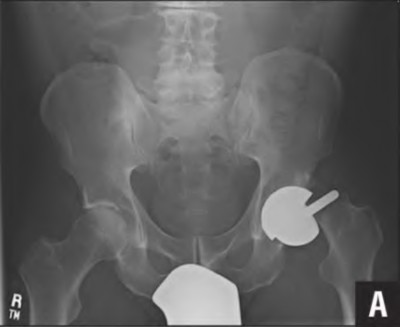

Question 32

A 45-year-old female with developmental dysplasia of the hip (DDH) presents for THA. Preoperative radiographs show the femoral head is subluxated, with 80% proximal migration relative to the height of the normal true acetabulum. Based on the Crowe classification, what type of dysplasia does she have?

Explanation